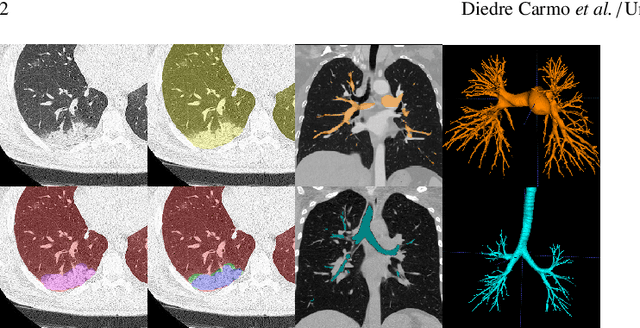

Abstract:The COVID-19 pandemic response highlighted the potential of deep learning methods in facilitating the diagnosis and prognosis of lung diseases through automated segmentation of normal and abnormal tissue in computed tomography (CT). Such methods not only have the potential to aid in clinical decision-making but also contribute to the comprehension of novel diseases. In light of the labor-intensive nature of manual segmentation for large chest CT cohorts, there is a pressing need for reliable automated approaches that enable efficient analysis of chest CT anatomy in vast research databases, especially in more scarcely annotated targets such as pneumonia consolidations. A limiting factor for the development of such methods is that most current models optimize a fixed annotation format per network output. To tackle this problem, polymorphic training is used to optimize a network with a fixed number of output channels to represent multiple hierarchical anatomic structures, indirectly optimizing more complex labels with simpler annotations. We combined over 6000 volumetric CT scans containing varying formats of manual and automated labels from different sources, and used polymorphic training along with multitask learning to develop MEDPSeg, an end-to-end method for the segmentation of lungs, airways, pulmonary artery, and lung lesions with separation of ground glass opacities, and parenchymal consolidations, all in a single forward prediction. We achieve state-of-the-art performance in multiple targets, particularly in the segmentation of ground glass opacities and consolidations, a challenging problem with limited manual annotation availability. In addition, we provide an open-source implementation with a graphical user interface at https://github.com/MICLab-Unicamp/medpseg.